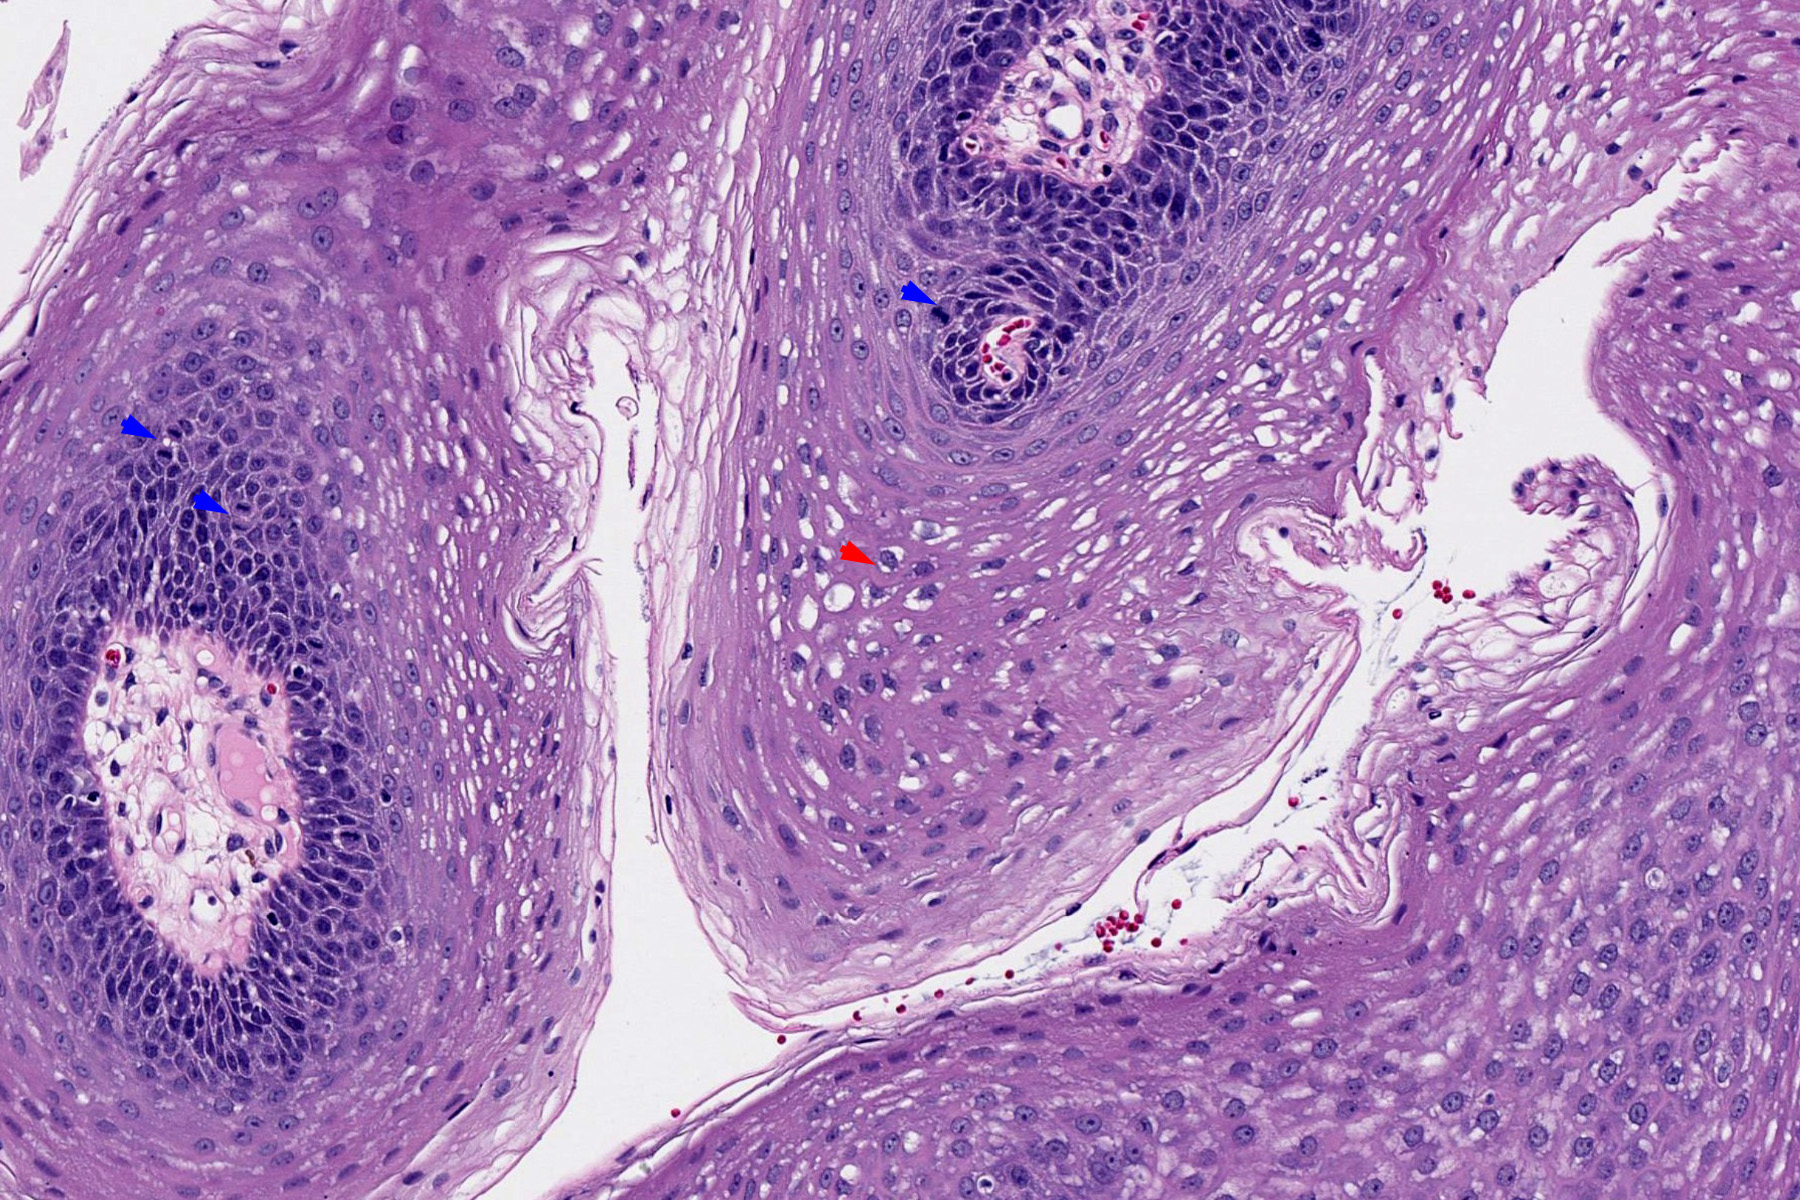

Microscopic (histologic) description

- Finger-like projections or multiple fronds with a central fibrovascular core, covered by benign hyperplastic stratified squamous epithelium

- Basal and parabasal hyperplasia

- Increased mitotic figures in the basal and parabasal layers

- Koilocytic changes in upper layer: may be pronounced or subtle

- Surface keratinization: absent to minimal

- Malignant transformation is characterized by aberrant (paradoxical) keratinization, marked cytological atypia, focal necrosis, increased mitoses and atypical mitoses not limited to the basal and parabasal layers, as well as invasive growth pattern (Respir Med 2017;126:116)

Microscopic (histologic) images